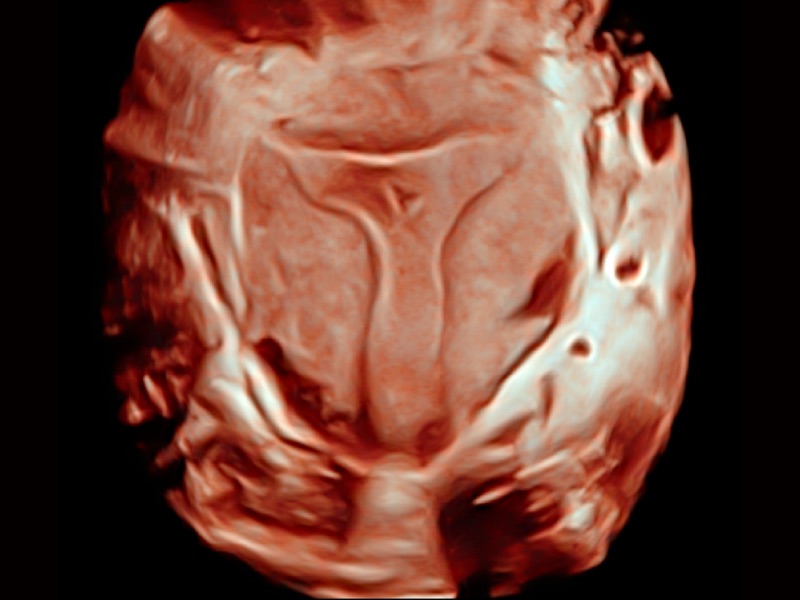

• S-Live Silhouette

A través de la aplicación de una fuente de luz virtual y un efecto de sombra, S-Live Silhouette ve a través de la superficie y delinea claramente los contornos de huesos, órganos, cavidades, paredes de los vasos y otras estructuras internas. Es una herramienta beneficiosa para identificar anatomía normal y diagnosticar malformaciones congénitas complejas.

Renderizado de rostro fetal con S-Live